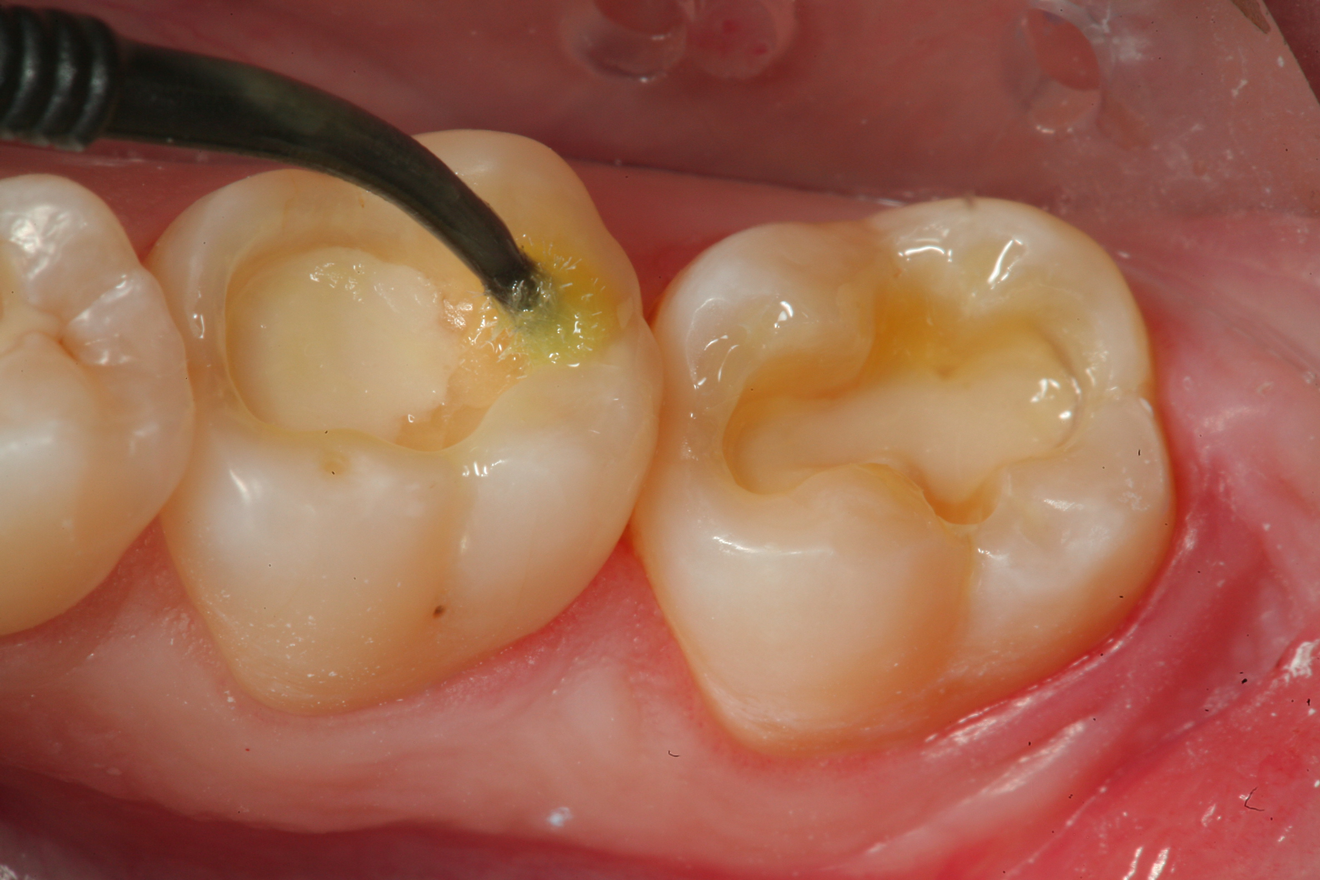

Fig 13. After controlling any bleeding from the exposure site with sodium hypochlorite on a cotton pellet,  a bioactive cavity liner (TheraCalTM LC, Bisco Dental Products) was then placed over the exposure site and light cured.  Next, a bioactive “dentin replacement” material (TheraBase, Bisco Dental Products) was used to base both cavity preparations to a more ideal depth just apical to the dentinoenamel junction.

Figure 13